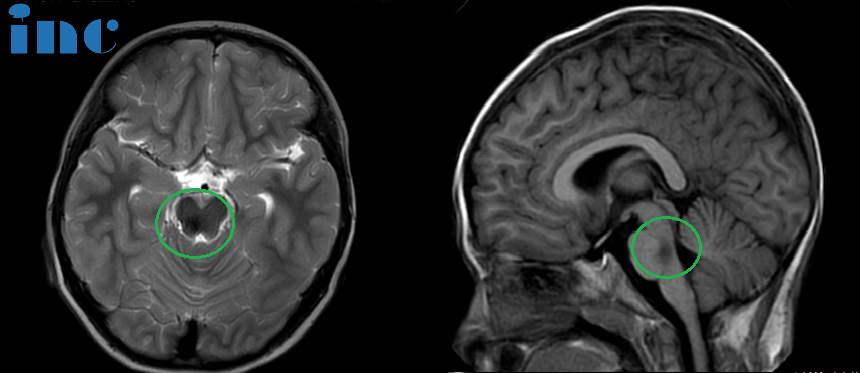

一名不到2岁的男童聪聪在苏州大学附属儿童医院接受脑干海绵状血管瘤切除术。患儿因看电视时出现斜视症状,经眼科检查后行脑部核磁共振,发现脑干存在16×22×21mm的血肿,第四脑室受压变窄。患儿表现为双眼斜视、面瘫、不自主扭头和行走不稳等脑干出血症状。

海绵状血管瘤(CMs)是可能导致反复出血的血管性病变,引起神经功能损害甚至死亡。脑干海绵状血管瘤占颅内海绵状血管瘤的20%,年出血率显著高于其他部位。脑干出血量超过一瓶盖容量即可导致死亡,早期诊断尤为重要。